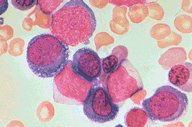

Acute non-lymphoblastic leukemia (M6)

(Erythroleukemia), high-oil mag

Acute non-lymphoblastic leukemia (M6).

(Erythroleukemia). This high-oil magnification

field shows the range of abnormalities seen in

erythroleukemia. Most blasts have marked

nuclear dyspoiesis. Some are vacuolated. The

central blast could be myeloid.